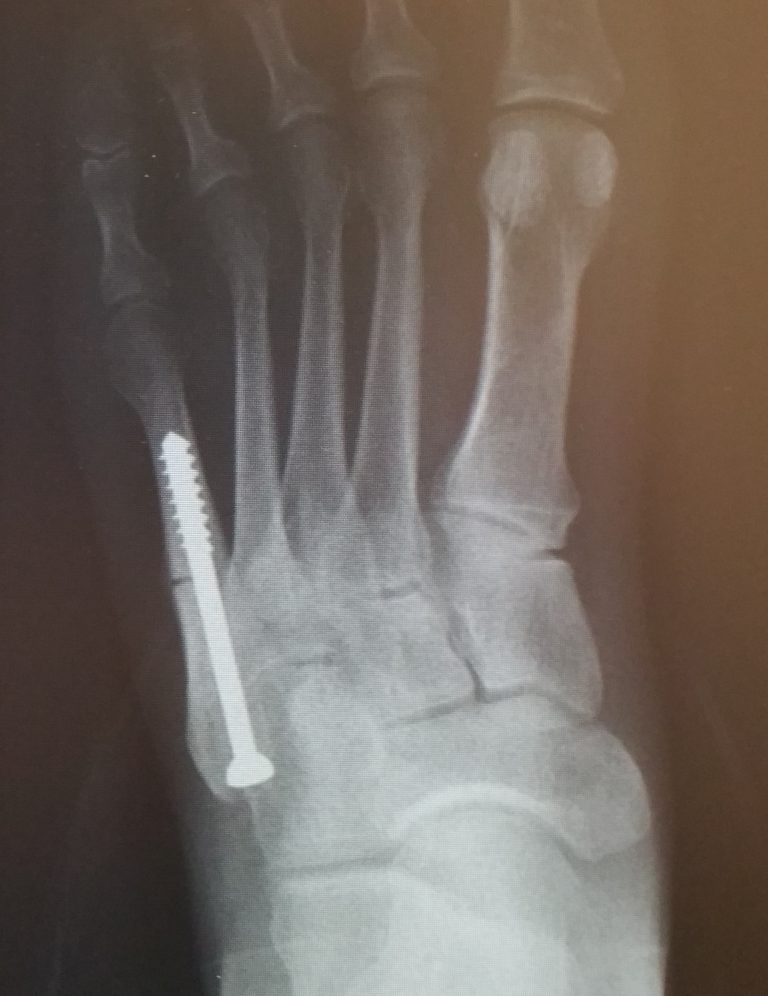

Metatarsal Shaft Fractures FootEducation